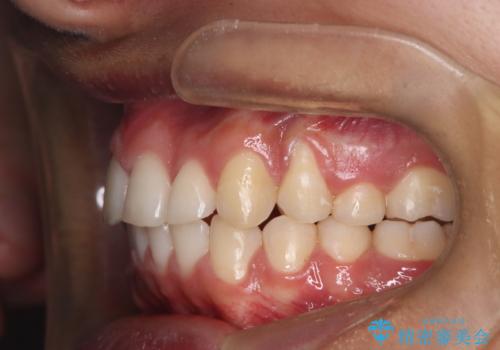

- 咬み合わせの不調和と歯並びのデコボコを主訴にご来院された患者様です。

精密矯正検査の結果、歯を抜かずに非抜歯でワイヤー矯正で治療を行う方針としました。

叢生(歯のデコボコ)の量が多く、加えてディープバイト(過蓋咬合)や重度の捻転も認められたため、リンガルアーチやマイクロインプラントなどの補助装置を併用し、治療を進めました。